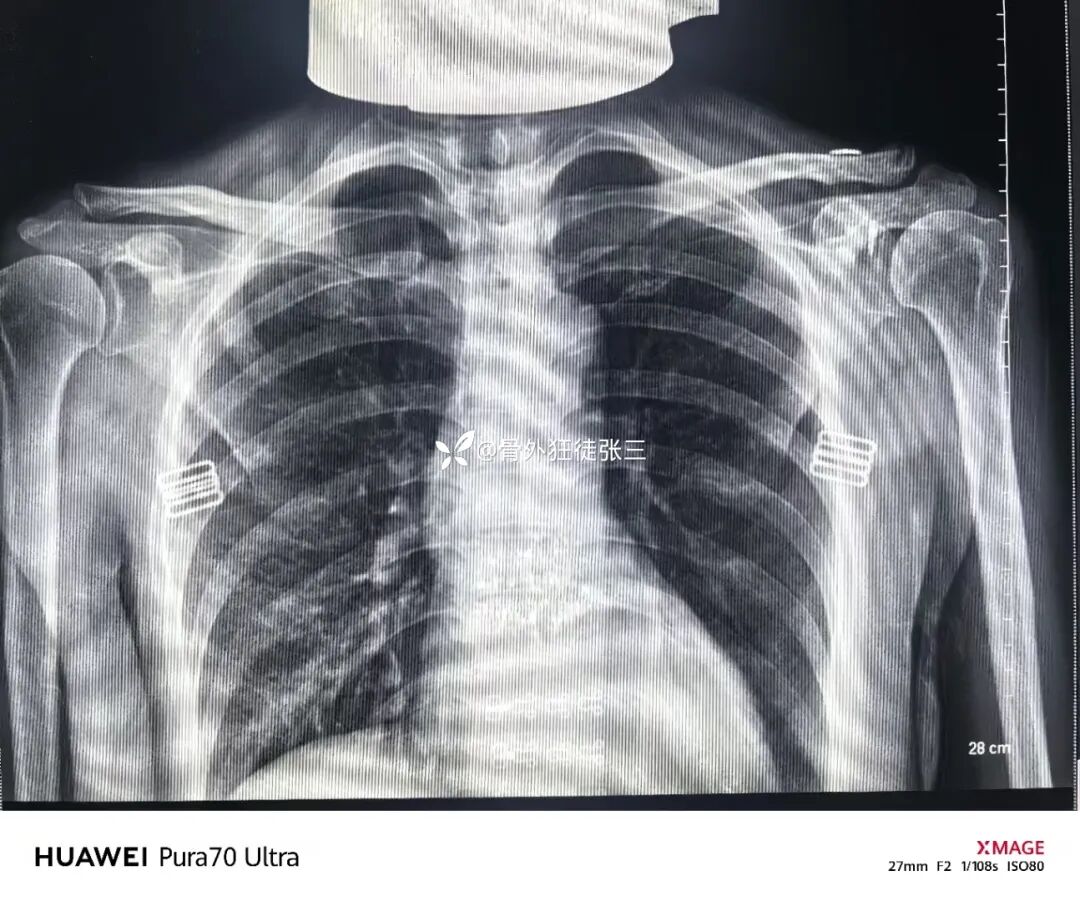

锁骨钩板使用不当术后的并发症实在太多了

肩峰撞击综合症,肩峰骨质的磨损吸收、肩峰下滑囊炎、冈上肌腱炎、近侧端因应力过大可致钢板断裂、板钉松动,甚至骨折

这些异常的摩擦均可刺激局部神经、导致疼痛的发生,从而影响患者功能的锻炼和恢复